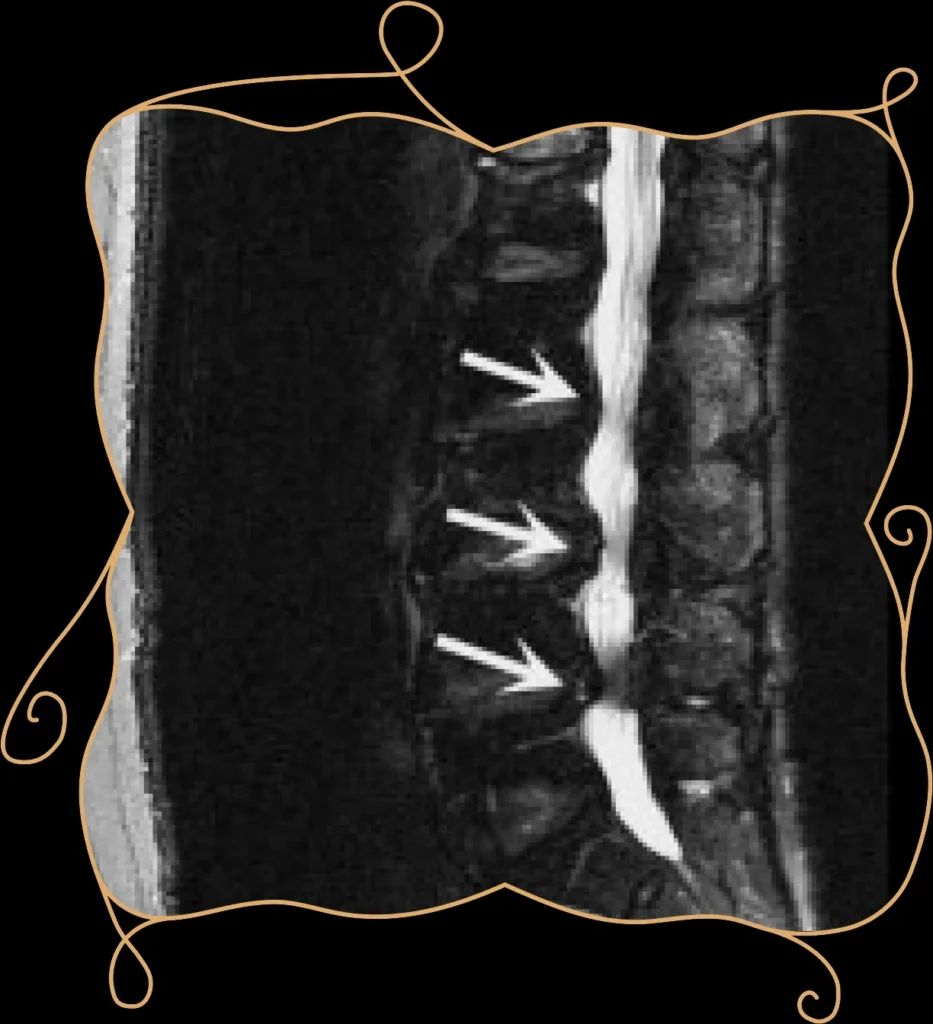

Η πλέον ενδεδειγμένη απεικονιστική εξέταση για τη διερεύνηση της παθολογίας της σπονδυλικής /τρηματικής στένωσης, είναι η μαγνητική τομογραφία (MRI) της οσφυϊκής μοίρας της σπονδυλικής στήλης (ΟΜΣΣ). Το πλεονέκτημά της σε σχέση με την αξονική τομογραφία, η οποία απεικονίζει καλά τις οστικές δομές της σπονδυλικής στήλης, είναι ότι η μαγνητική τομογραφία δείχνει σημαντικές λεπτομέρειες που αφορούν άλλες ευαίσθητες ανατομικές δομές, όπως είναι οι σύνδεσμοι, οι νευρικές ρίζες, οι μεσοσπονδύλιοι δίσκοι και ο νωτιαίος μυελός.

Εναλλακτικά, εφόσον ο ασθενής δεν μπορεί να υποβληθεί σε μαγνητική τομογραφία, η αξονική μυελογραφία είναι η εξέταση εκλογής. (CT μυελογραφία). Πριν την αξονική τομογραφία, σκιαγραφική ουσία, εγχύεται εντός του υπαραχνοειδούς χώρου της σπονδυλικής στήλης, όπου κυκλοφορεί το εγκεφαλονωτιαίο υγρό. Με τη χρήση της σκιαγραφικής ουσίας απεικονίζονται καλύτερα τα νεύρα και ο νωτιαίος μυελός.